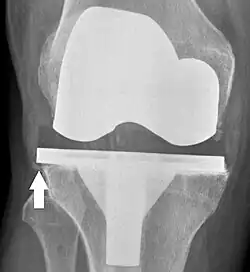

Loosening of the prosthesis can be indicated on X-ray by thin radiolucent spaces around the implant, or more obviously by implant displacement.[56]

Knee replacement is routinely evaluated by X-ray, including the following measures:

- FFC: frontal femoral component angle. It is typically regarded as optimal when being 2–7° in valgus.[63]

- FTC: frontal tibial component angle, which is regarded as optimal when being at a right angle. A varus position of more than 3° has generally been found to increase the failure rate of the prosthesis.[63] -

- Anterior femoral notching (the femoral component causing reduced thickness of the distal femur anteriorly), seems to cause an increased risk of fractures when exceeding about 3 mm.[64]

- LTC: lateral (or sagittal) tibial component angle, which is ideally positioned so that the tibia is 0–7° flexed compared to at a right angle with the tibial plate.[63]